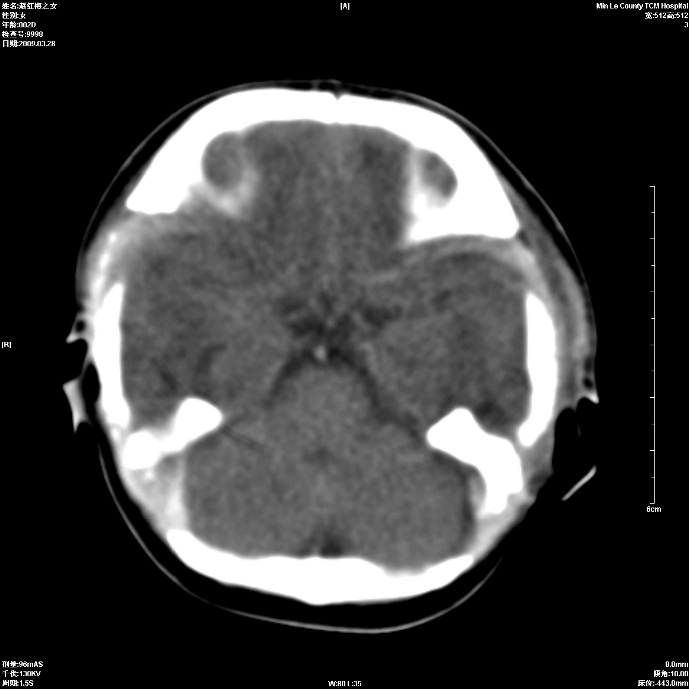

标题: PED1815:患儿出生两天,哭闹不安,囟门饱满 [打印本页]

标题: PED1815:患儿出生两天,哭闹不安,囟门饱满

少量蛛网膜下腔出血,有窒息史吗?

支持考虑新生儿缺血缺氧性脑病伴蛛网膜下腔出血,请结合临床,建议随访复查

缺血缺氧性脑病伴蛛网膜下腔出血.

支持缺血缺氧性脑病伴少量蛛网膜下腔出血。

支持 1)缺氧缺血性脑病。2)蛛网膜下腔出血。

蛛网膜下腔出血

z新生儿缺血缺氧性脑病,蛛网膜下腔出血!